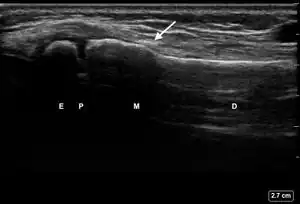

| 2 | Buckle (Torus) Fracture | "Bent" | ![]() Ultrasound dorsal view of buckle fracture of radius (shown by arrow). E = epiphysis; P = physis; M = metaphysis; D = diaphysis. | ||